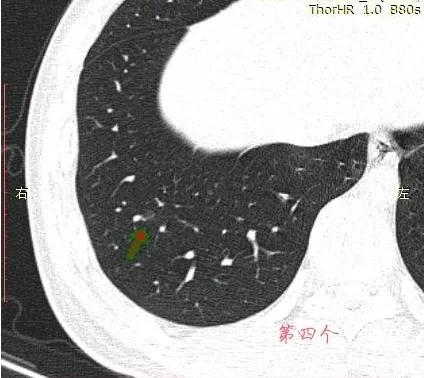

在11月16号,自己担心去了一趟胸外科门诊,医生看了片子之后直接让我复查胸部平扫➕HRCT,看了复查片子之后医生问过我也没有家族史,随后医生说癌症可能性非常大,并且已经说到要手术和靶向药治疗。但还是让我吃半个月莫西沙星,由于当地拜复乐没买到,就吃了其他牌子的莫西沙西,最后网购吃了三颗拜复乐!距离复查只有一周,这个月以来一直焦虑。因为双肺足足有四个磨玻璃结节,在网上看到戴主任的专业,希望能够得到戴主任的建议,4个结节冷月都帮我截图了,我放在下面,麻烦戴主任帮我看看!

左肺的,已有事。右肺,没啥事。

左肺结节,至少微浸润腺癌。右侧结节良性的。